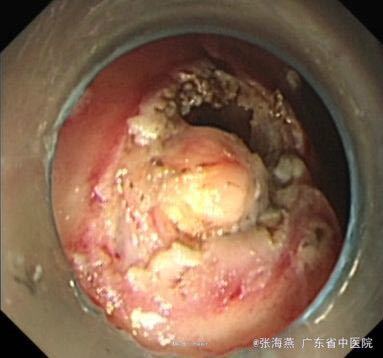

体格检查:BP:146/87mmHg;腹平坦,未见胃肠型及蠕动波,腹软,未扪及包块,上腹部轻压痛,无反跳痛,肝脾肋下未扪及,肝肾区无叩击痛,麦氏征(-),莫非氏征(-),移动性浊音(-),肠鸣音5次/分。 辅助检查:血型:B型,RhD阳性;血常规、二便常规、凝血、生化、肝功、CEA、CA199、输血4项未见异常。心电图:窦性心律,心脏逆钟向转位。胸片:主动脉硬化;胸椎退行性变。B超:胆囊壁稍毛糙,肝脏、胰腺、双肾、膀胱未见明显异常。超声胃镜:胃底固有肌层隆起:符合胃底间质瘤改变;慢性浅表性胃窦炎。

诊断:1.胃底间质瘤(ESD术后);2、慢性胃炎;3、高血压病2级;4、颈椎退行性变。 治疗:治疗上,行ESD术切除胃底肿物,术后予明可欣静滴预防感染,潘妥洛克静滴抑酸护胃,铝镁加混悬液口服保护胃粘膜,以及补液营养支持治疗。术后病理提示:符合胃肠道间质瘤(低级别,无风险);经治疗后,患者无特殊不适,予出院。